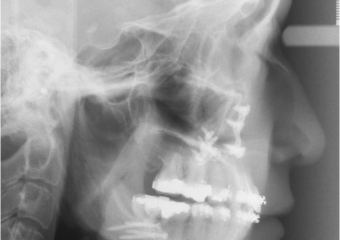

Telerradiografia inicial